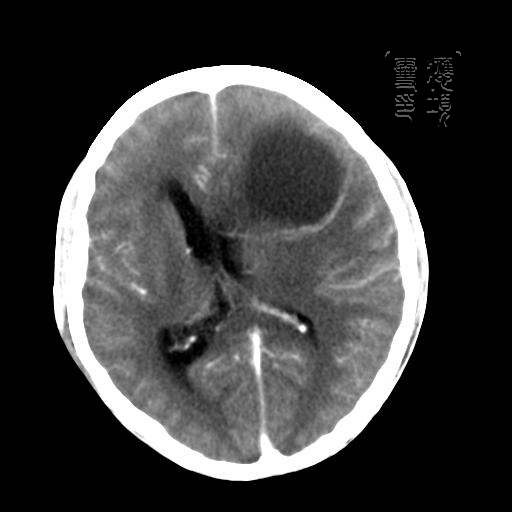

m 52y

二月前癫痫入院, 无既往史,现头痛、呕吐、视力减退、复视行ct平扫及增强检查。

见环形,结节样强化,考虑囊性星型细胞瘤。

考虑囊性星型细胞瘤,ct征象大囊小结节.

左额叶囊实性占位,以囊性为主,并见明显强化不规则壁结节,占位效应明显,首先考虑是囊性星形细胞瘤.